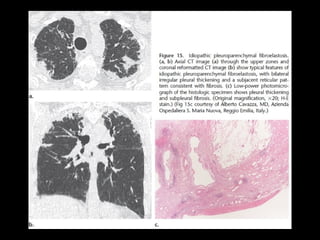

Fibroelastosis

pleuroparenquimatosa idiopática

• Rara

• Fibrosis pelura y subpleura LS

• 60% progresa y 40% muere

• CT:

• Engrosamiento pelural irregular y “tags” y fibrosis

• Pérdiad de volumen de LS, Bq por tracción

• DD: fibrosis pulmonar familiar, tejido conectivo (espondilitis

anquilosante), sarcoidosis fibrótica, neumonitis por

hipersensibilidad

Fibroelastosis pleuroparenquimatosa idiopática • Rara •Fibrosis pelura y subpleura LS • 60% progresa y 40% muere • CT: • Engrosamiento pelural irregular y “tags” y fibrosis • Pérdiad de volumen de LS, Bq por tracción • DD: fibrosis pulmonar familiar, tejido conectivo (espondilitis anquilosante), sarcoidosis fibrótica, neumonitis por hipersensibilidad